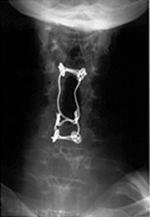

Middle-aged woman with rheumatoid arthritis and unstable atlantoaxial (C1-2) subluxation. Note the wide separation between the odontoid and the anterior ring of C1. The cervical spine was stabilized with an occipital strut held in place by occipital screws and rods extending from the occiput to C2. Lateral mass screws are present connecting to the rods at C2, and there is also posterior spinal wiring. |